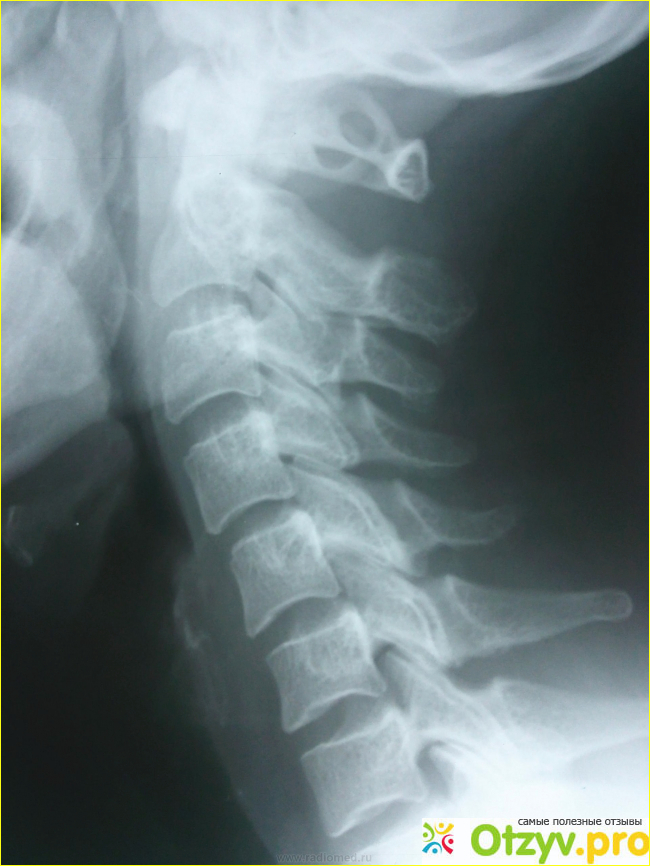

Диагностика затруднений не вызывает: патология хорошо видна на рентгенограмме шейного отдела позвоночника.